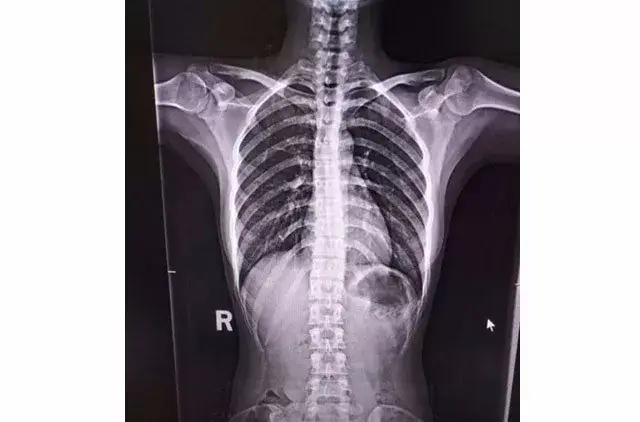

驼背x光图

从x光胸椎侧位片上看,她的驼背程度达到了中重度.